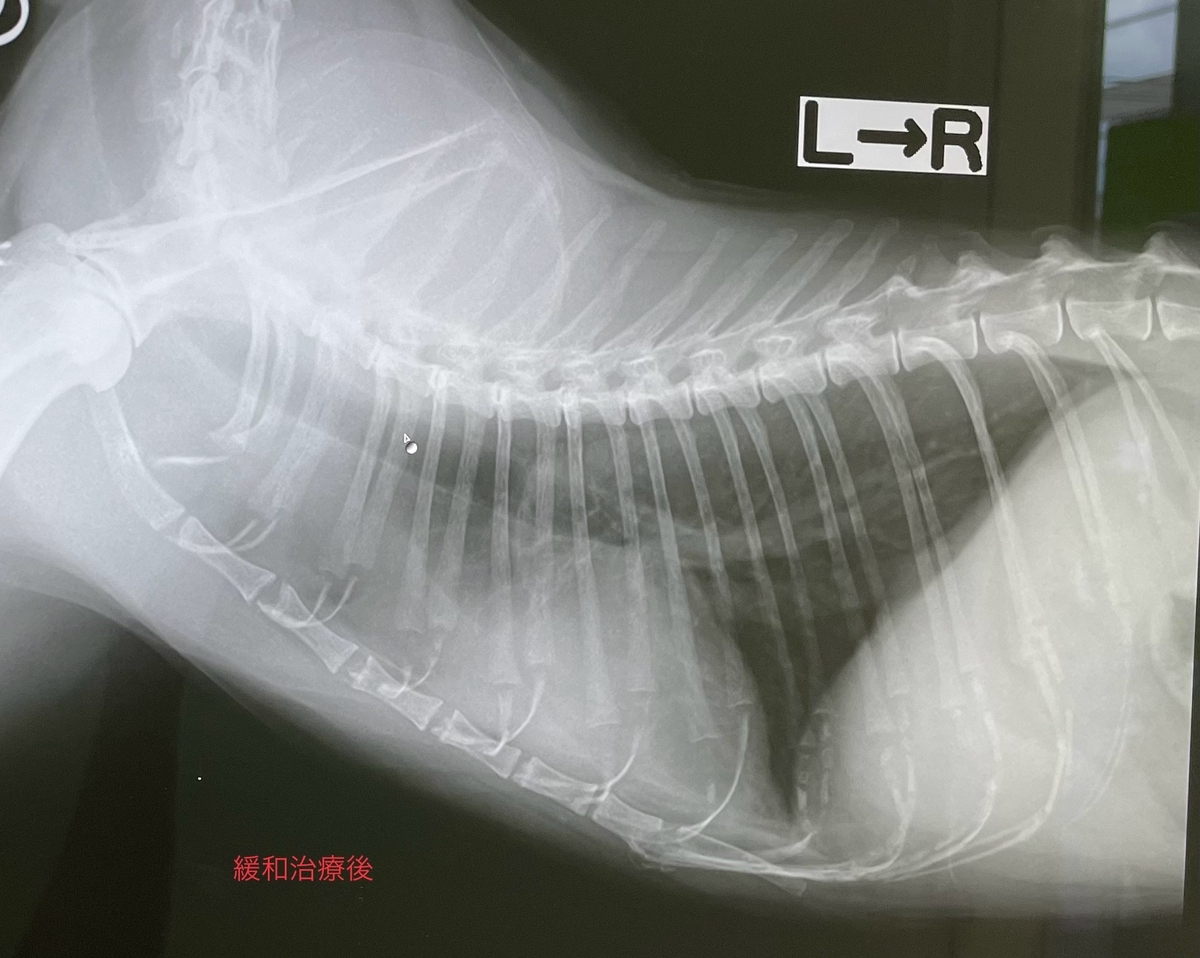

胸腺腫の根治治療として、外科摘出があります。様々な理由で、外科が行えない場合は、緩和治療として、ステロイドの内服をおこないます。

この猫ちゃんは17才、CT検査にて線維素性胸膜炎の発症、腹側胸膜への浸潤、前大静脈、腕頭動脈、右心房と癒着しており、手術のリスクが高い為、緩和治療となりました。

現在ステロイド内服で1年経過しています。